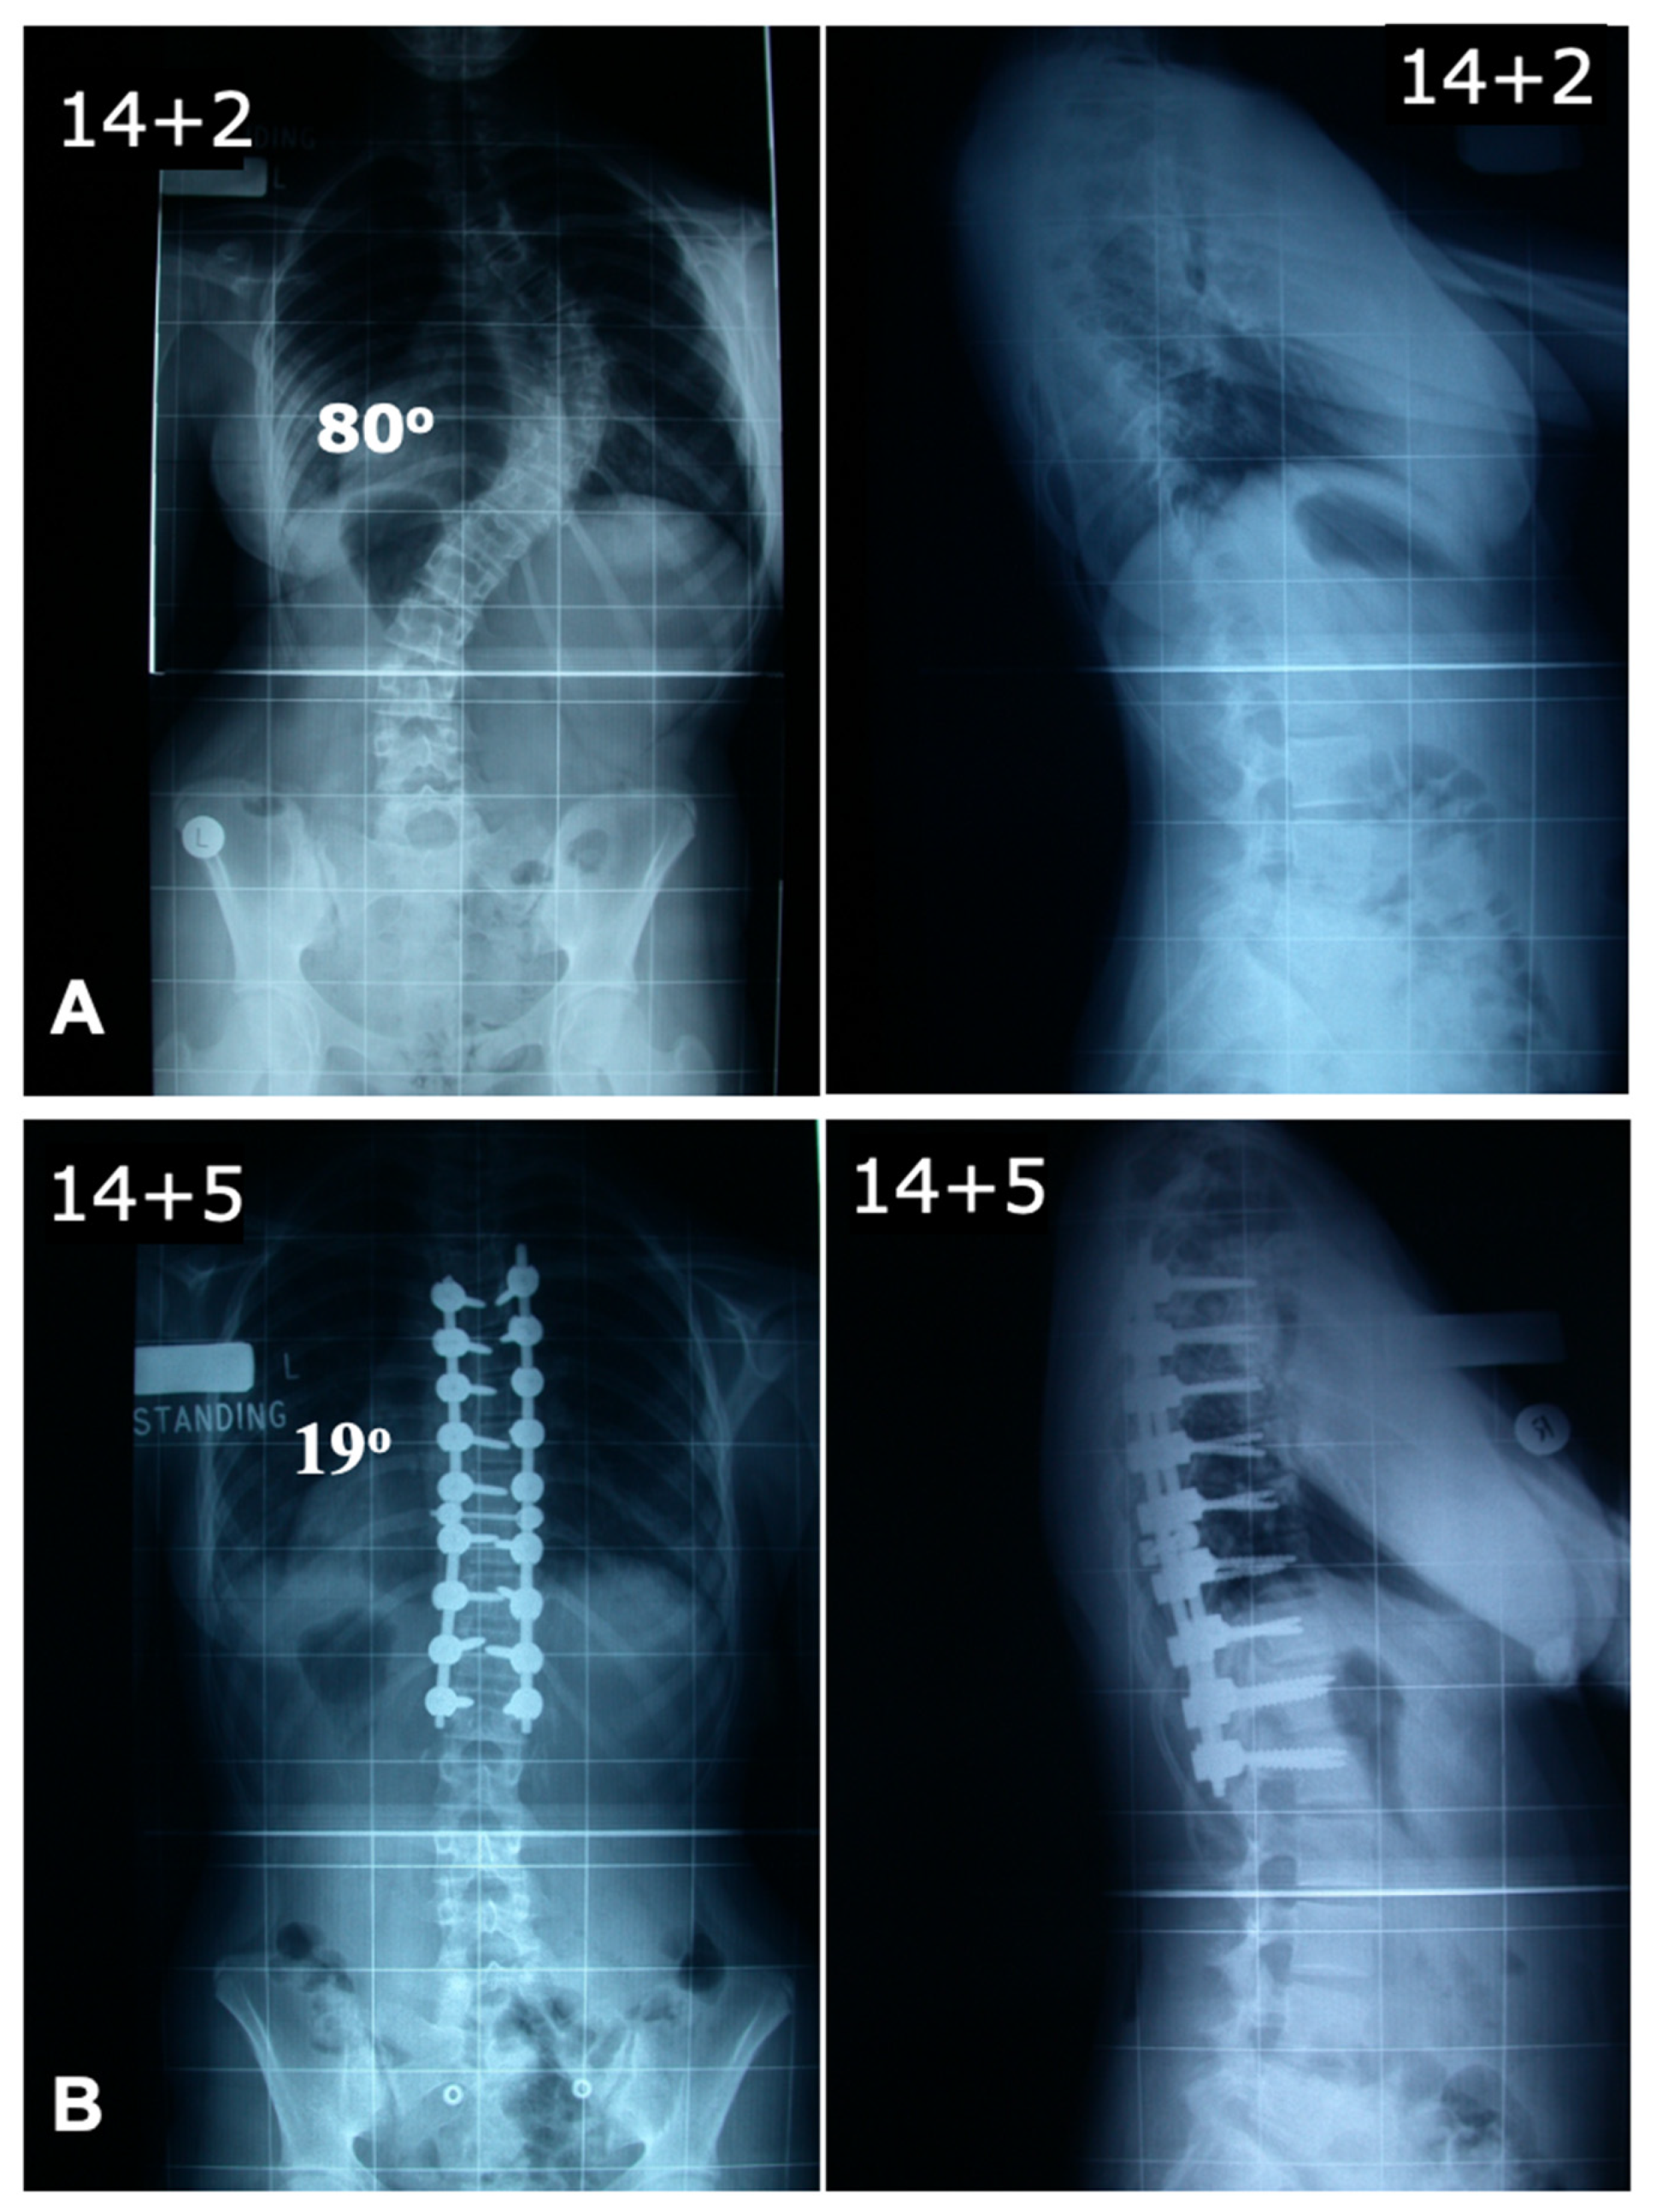

The global rod derotation technique, originally introduced by Cotrel and Dubousset, is based on the concept that the coronal deformity typical in AIS approximates the desired sagittal alignment when rotated 90° [51]. This method involves inserting a rod pre-contoured to the ideal sagittal shape on the curve’s concavity. The anchors are loosely attached to the rod and then rotated 90° along the axial plane to transform the coronal deformity into sagittal alignment [52,53]. The traditional use of the concave side for scoliosis correction poses challenges due to anatomical constraints. Studies, including that by Liljenqvist et al., reveal significantly narrower pedicles on the concave side at the thoracic curve apex, increasing the risk of cortical wall penetration [54]. Anekstein et al. evaluated the use of a convex rod derotation technique for correcting AIS in 40 patients treated with all-pedicle screw constructs and followed for two years. The mean preoperative Cobb angle of 60° improved to 17° postoperatively, with a 7% correction loss at follow-up, yielding a 71% major curve correction. The technique showed comparable outcomes to traditional concave-side corrections, with additional benefits of reduced neurological risks due to safer screw placement on the convex side. Thoracic kyphosis decreased slightly, and no major complications, infections, or revisions were reported [55]. This approach benefits from the stability offered by multiple fixation points, distributing mechanical stress and reducing localized anchor strain. It is particularly effective for thoracic hypokyphosis, enabling simultaneous correction in both the coronal and sagittal planes. However, this technique does not correct axial plane deformities. Advanced imaging has shown that while previously thought to induce rotational correction at the apex, it primarily results in translational adjustment. Additionally, the ideal sagittal contour may not align with the coronal deformity, potentially leading to suboptimal sagittal apex placement post-rotation [46,56]. A case example is shown in Figure 2.